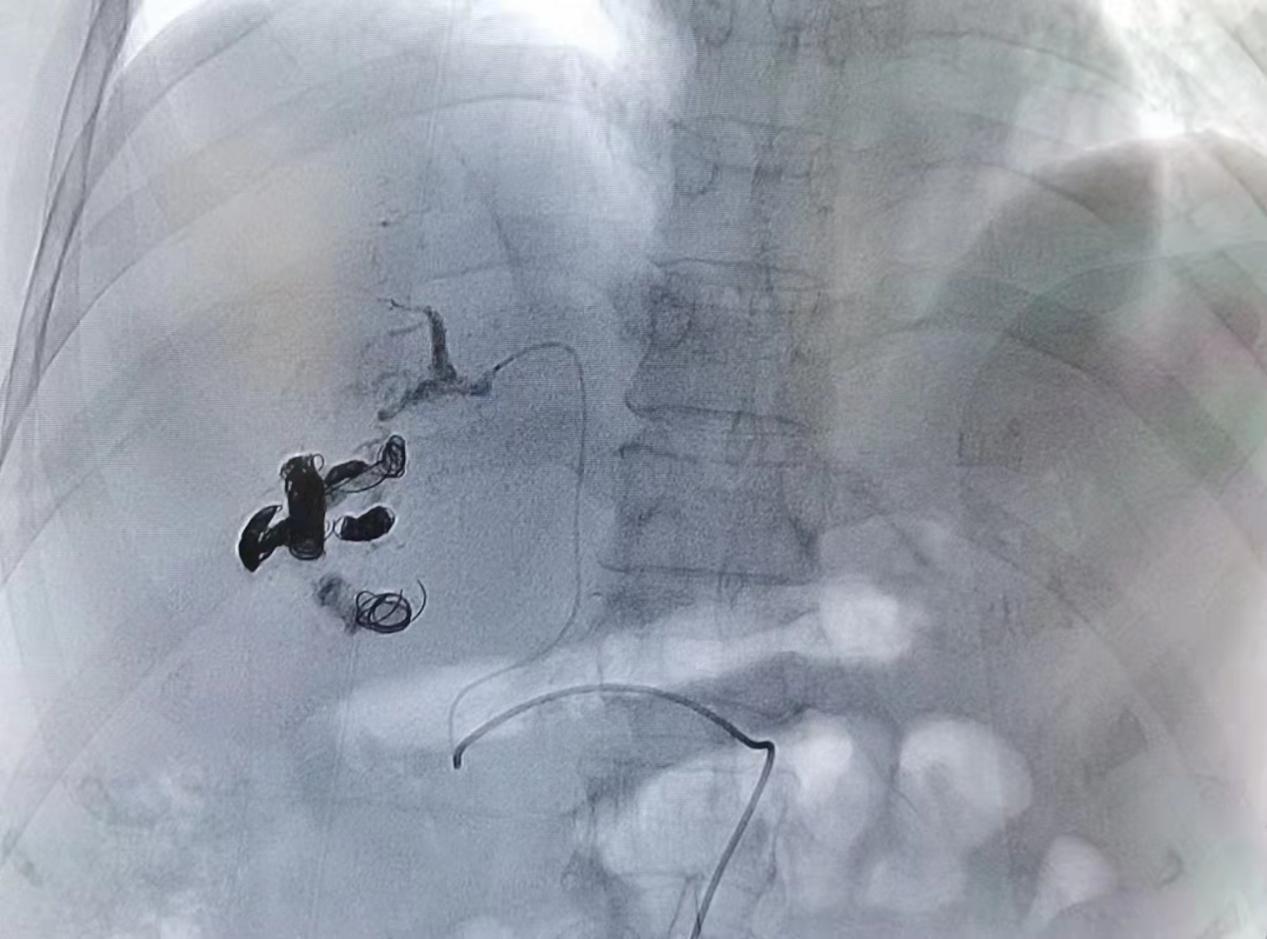

图三、四:弹簧圈联合组织胶栓塞靶血管